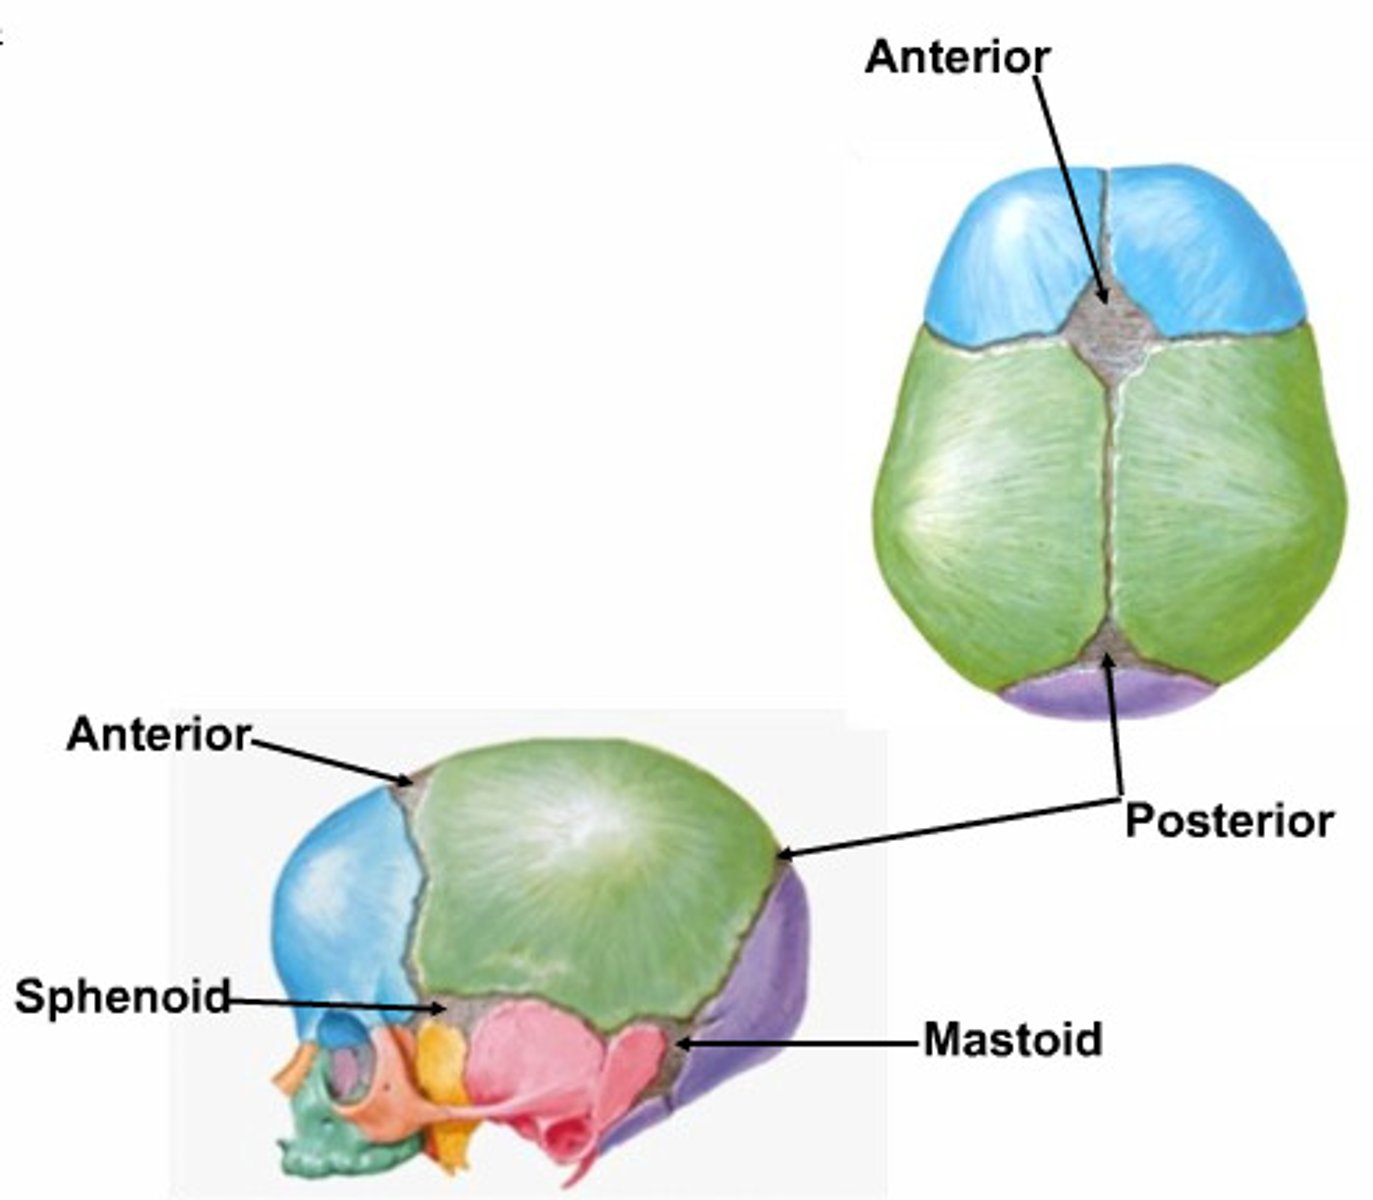

What is the calvarium?

skull cap, portion of neurocranium consisting of the frontal, parietal and occipital bones

What is the cranial base?

floor of the neurocranium, consisting of all the neurocranial bones

coronal suture

the suture between the parietal and frontal bones of the skull

sagittal suture

between the two parietal bones

lambdoid suture

between parietal bones and occipital bone

What are the features of the neonate skull?

large cranium and small face, mandibular division that fuses into mandibular symphysis, prominent fontanelles

What are fontanelles?

fibrous membranes connecting the cranial bones, anterior, posterior, sphenoid and mastoid

the premature ossification of 1 or more sutures resulting in bulging at the fontanelle at the contralateral side. Treated by helmets and or surgery

metopic craniosynostosis

fusion of the frontal suture resulting in elongation at the forehead

Sagittal Craniosynostosis

premature closure of sagittal suture resulting in posterior elongation

unicoronal craniosynostosis

one-sided closure of the coronal suture resulting in bulging at the contralateral forehead

lambdoid craniosynostosis

closing of one side of the lambdoid suture resulting in posterior bulging at the contralateral side